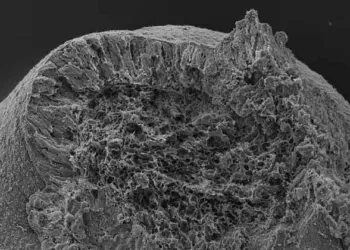

മനുഷ്യ ഭ്രൂണങ്ങളെ വികസിപ്പിക്കുന്നതിനായുള്ള ടിഷ്യു സംഘടിപ്പിക്കുന്നതില് നിര്ണായക പങ്ക് വഹിക്കുന്ന ശരീര ഭാഗമാണ് നട്ടെല്ലില് കാണപ്പെടുന്ന ഭ്രൂണത്തെ വളര്ച്ചയില് സഹായിച്ച ശേഷം ് ഇത് സുഷുമ്നാ ...